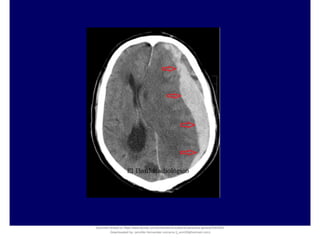

Subacute and chronic SDH appear as isodense or hypodense crescent-shaped lesions

that deform the surface of the brain

Multiple Densities of the Chronic Subdural Hematoma in CT Scans. Department of Neurosurgery, Soonchunhyang University

Cheonan Hospital, Cheonan, Korea. J Korean Neurosurg Soc 54 : 38-41, 2013